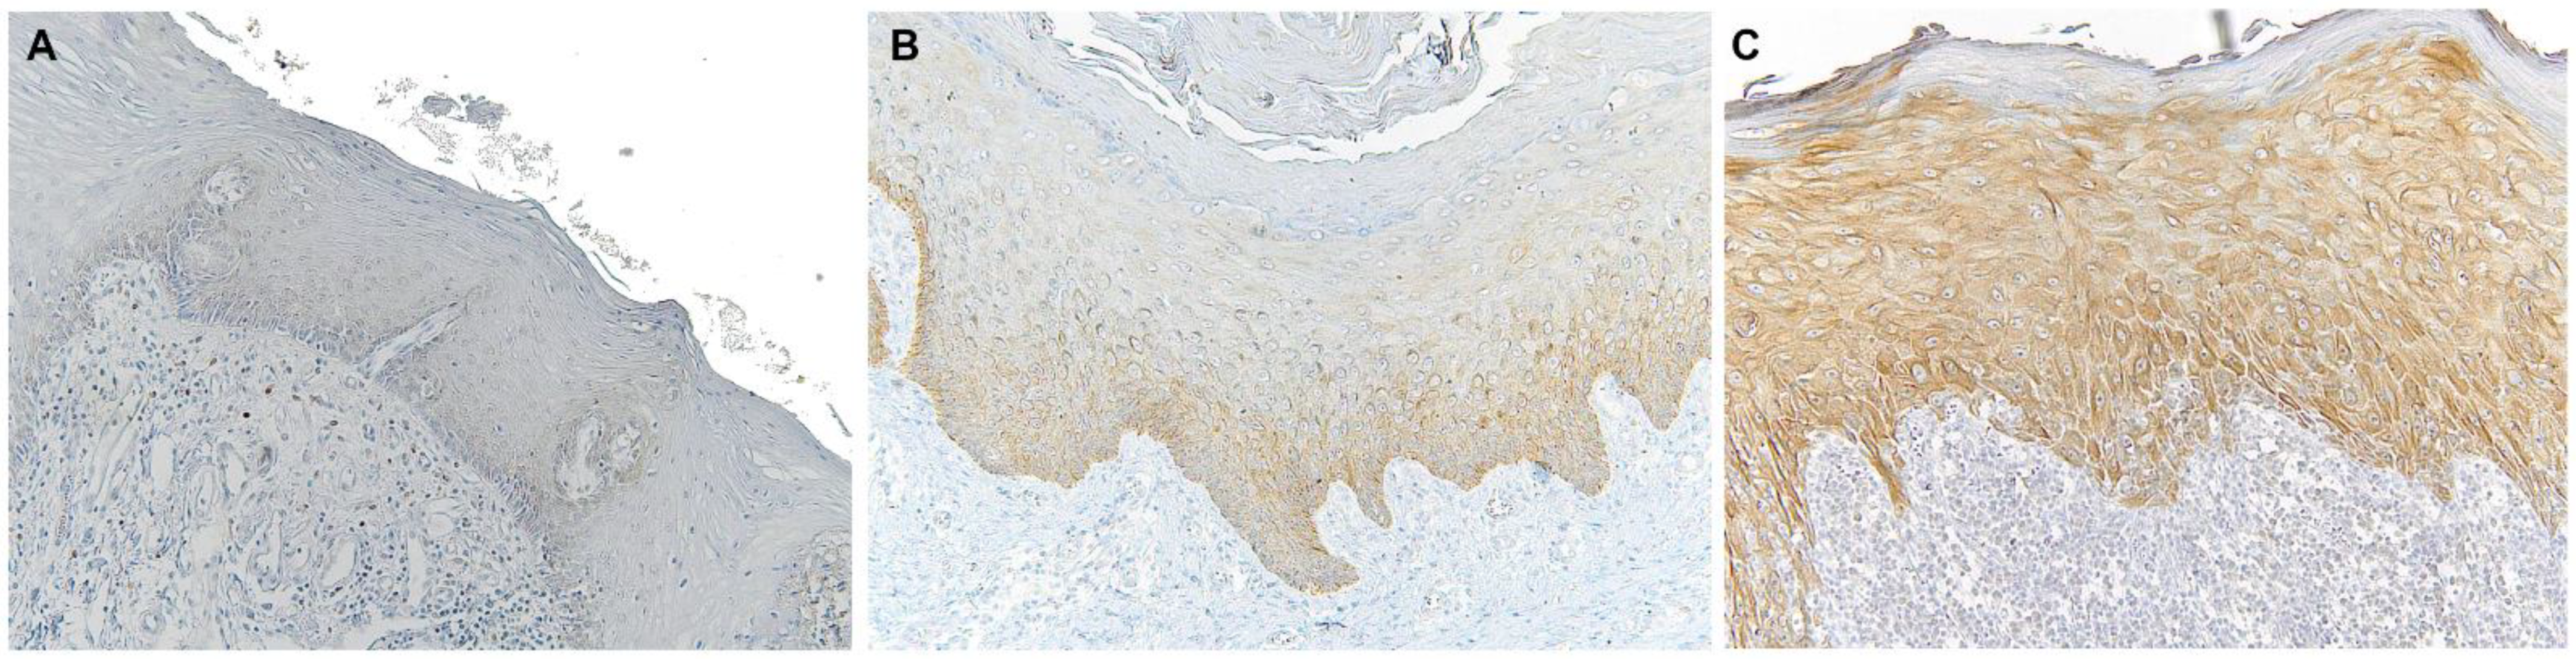

| Normal Oral Mucosa Control (NOC) | 30 | 3.53 | 3.84 | 0.0 | 15.0 | 15.00 |

| Non-Lichenoid Epithelium Surrounding OSCC (NLES-OSCC) | 38 | 21.72 | 54.80 | 0.0 | 300.0 | 300.00 |

| Lichenoid Epithelium Surrounding OSCC (LES-OSCC) | 28 | 63.11 | 65.48 | 0.0 | 255.0 | 255.00 |

| OSCC Ex Non-Lichenoid Lesion | 30 | 155.17 | 105.57 | 0.0 | 300.0 | 300.00 |

| OSCC Ex Lichenoid Lesion | 24 | 135.21 | 87.32 | 0.0 | 300.0 | 300.00 |